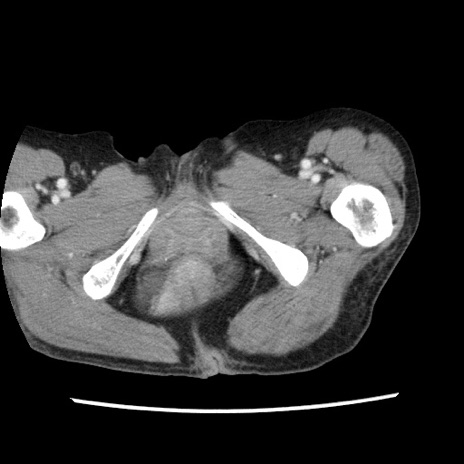

矢状断像

【症例】80歳代女性

【主訴】腹痛

【現病歴】8時間前から腹痛あり来院。

【既往歴】糖尿病、脂質異常症、子宮体癌にて子宮全摘術

【身体所見】意識清明・会話良好だが腹痛で苦悶様、全腹部にわたって反跳痛と圧痛あり

【データ】WBC 13600、CRP 0.14、LDH 224、CK 90